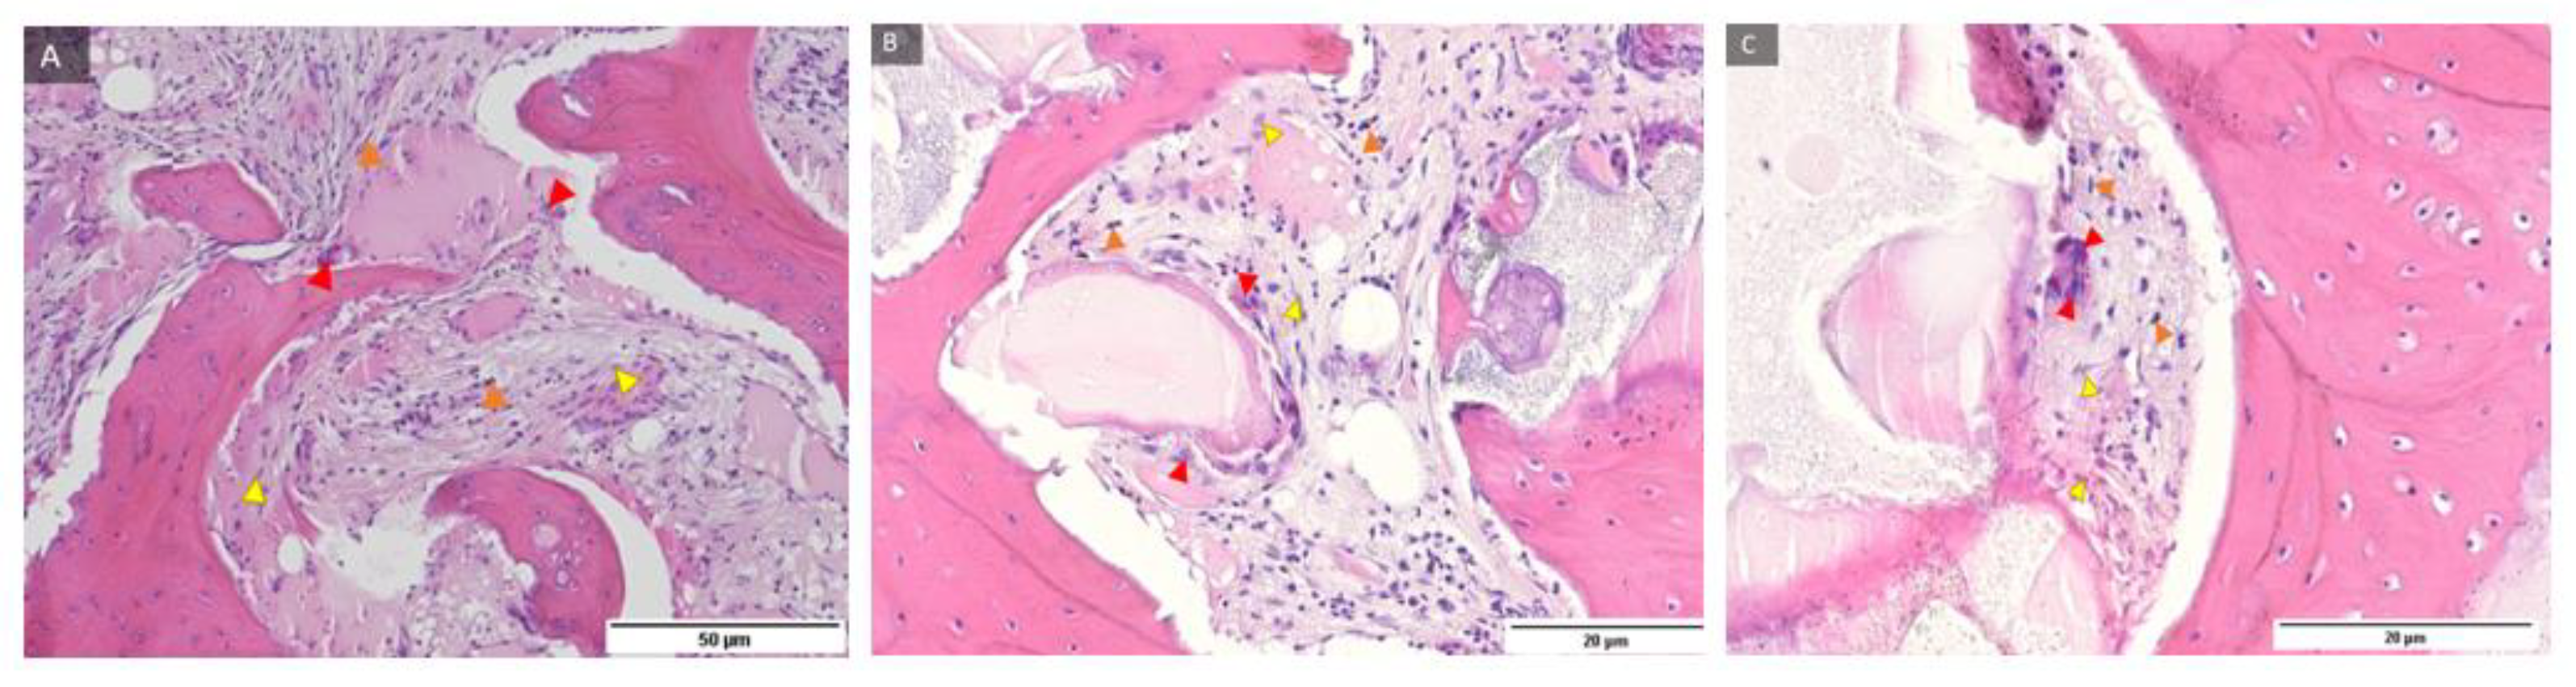

HE histological Staining